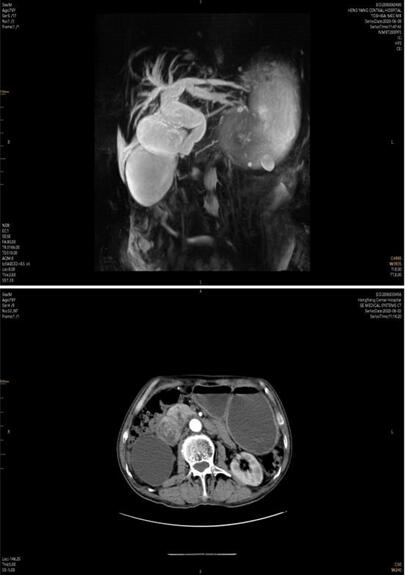

患者家屬經(jīng)多方打聽,赴我院胃腸外科會診。譚曙光主任及賀賽奇副主任閱外院腹部CT片,考慮十二指腸惡性腫瘤合并梗阻可能性大,唯有手術(shù)治療方為解決患者病癥最好方式??紤]患者高齡,全身營養(yǎng)狀況差,脫水及貧血嚴重,予積極補液、維持水電解質(zhì)平衡、腸外營養(yǎng)支持及輸血治療同時,完善術(shù)前相關(guān)輔助檢查。上腹部增強MRI+MRCP檢查提示:十二指腸水平段腫瘤,侵犯膽管下段、胰頭、橫結(jié)腸系膜,并周圍多發(fā)淋巴結(jié)腫大。十二指腸鏡下活檢病理:十二指腸粘膜慢性炎。